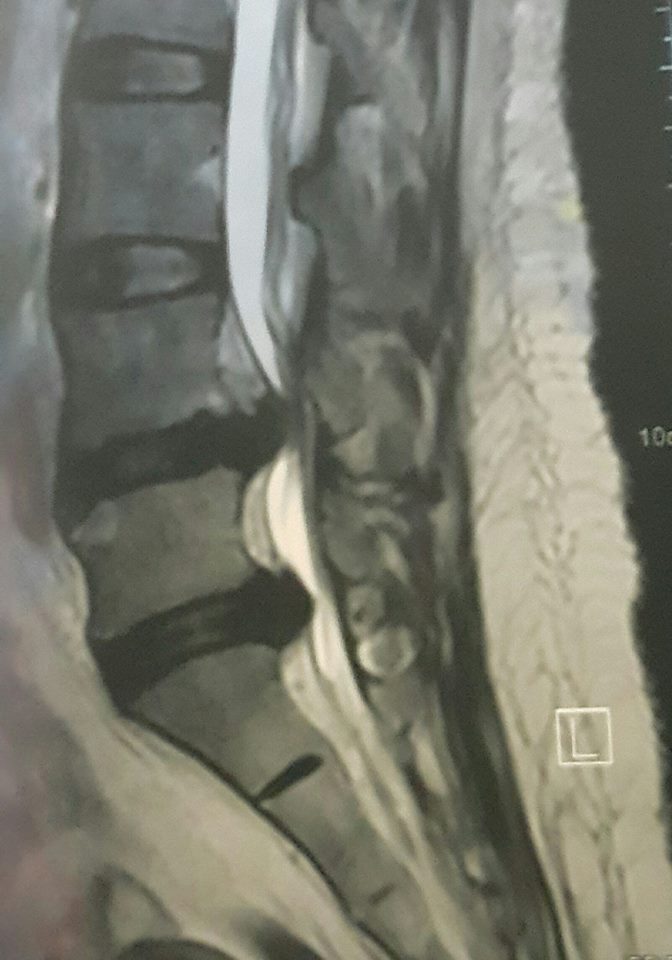

Its quite miracle

But with Allah's will anything is possible

Again..huge slipped disc treated well with laser injection PLDD..

Alhamdulillah syukur....